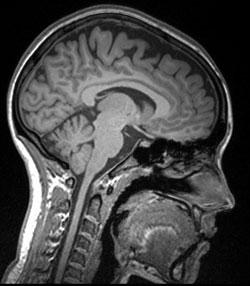

Resonancia magn tica nuclear

(ID 1732)

Resultado de la resonancia magn tica nuclear

(ID 2010)